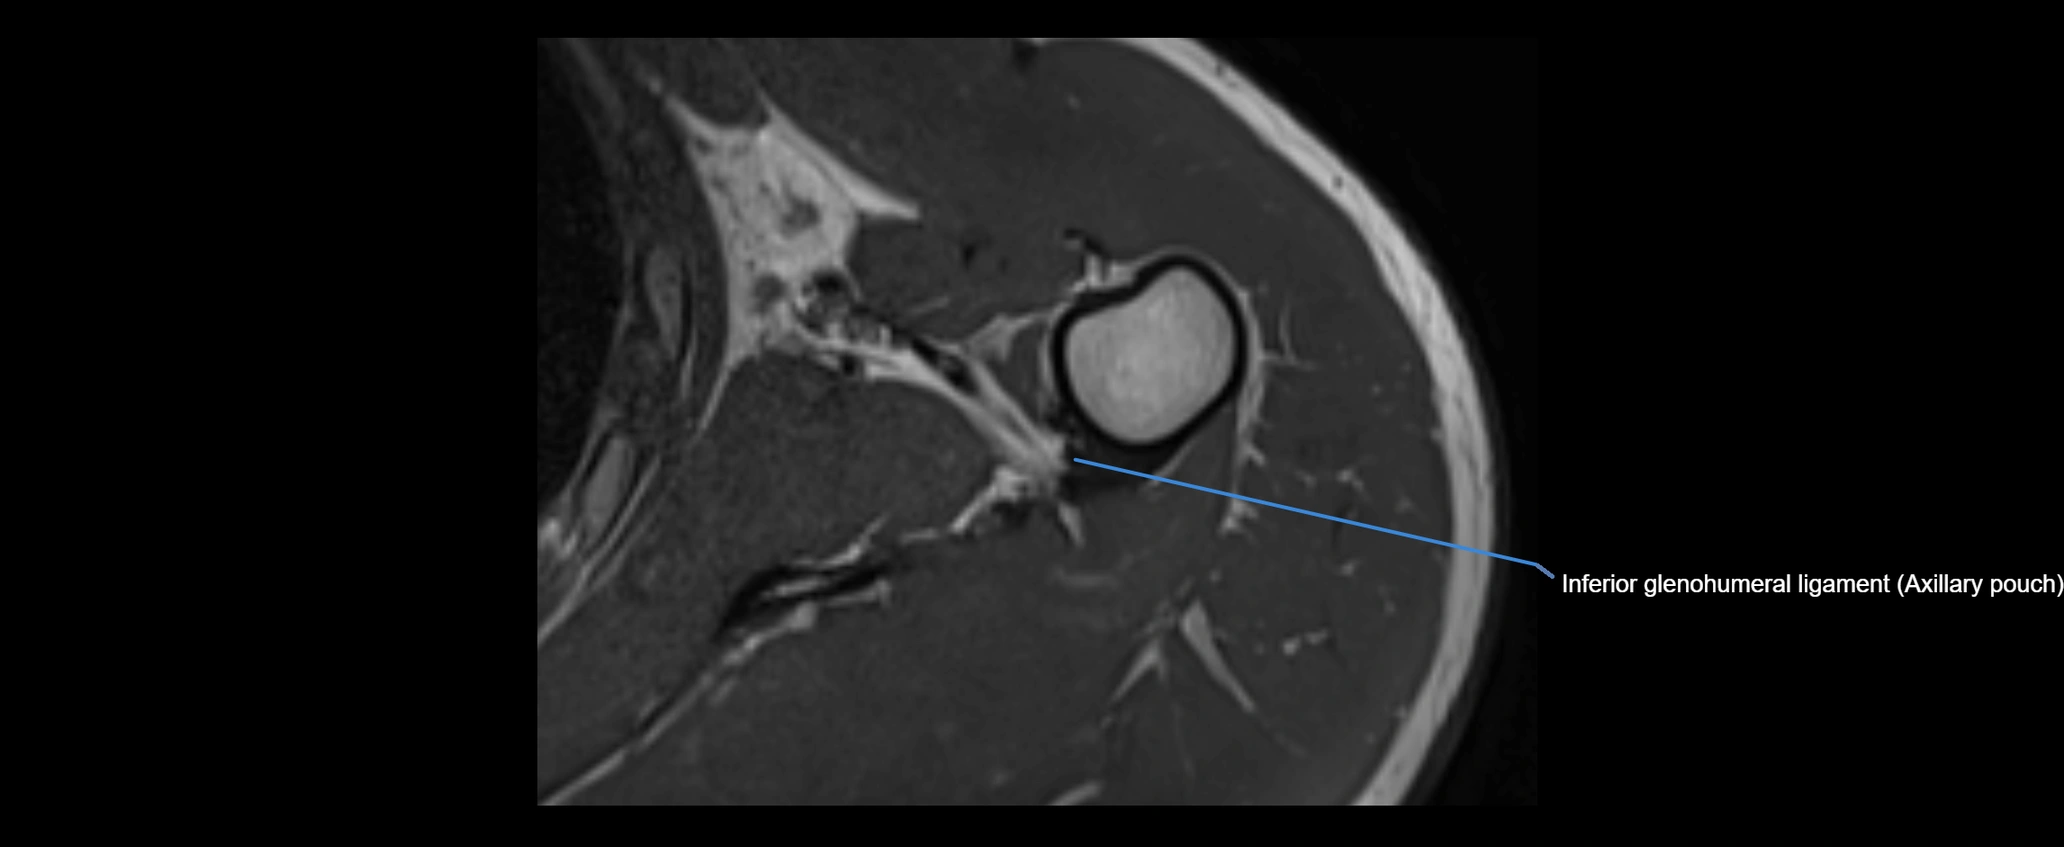

CT image

image